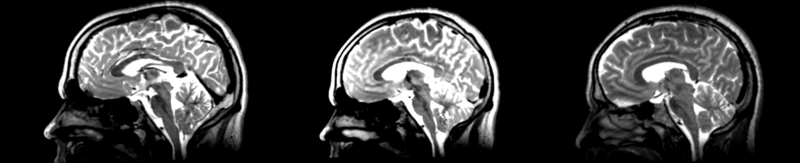

Registration of two different subjects t2 images via the pipe bspline selection in the Register Images module.

current20:38, 22 April 2009Thumbnail for version as of 20:38, 22 April 20092,100 × 427 (481 KB)Rauscha (talk | contribs)Registration of two different subjects t2 images via the pipe bspline selection in the Register Images module.